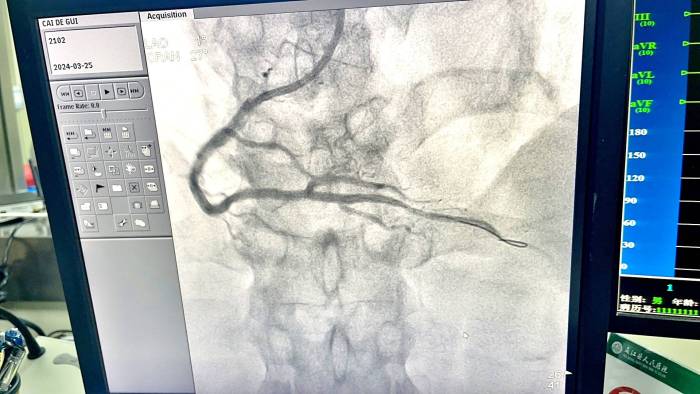

13:17转运患者到达县医院,等候在急诊科门口的医护人员直接护送患者绕行急诊科及心内科(CCU)直达导管室。13:18急诊造影提示:三支血管严重病变,右冠远端完全闭塞。13:33导丝通过闭塞病变血管,术中患者出现再灌注心律失常,经球囊扩张,植入支架1枚后患者转危为安。在谷硐卫生院、县急诊科、心内科和介入导管室的共同努力下,患者从胸痛救治单元入门到出门时间(DIDO)仅用了13分钟,从入PCI医院大门到导丝通过时间(D-to-W)仅为16分钟,高效联动的救治不仅抢救了患者的生命,还为患者挽救了更多存活心肌,给患者带来了良好的预后。

支架术后

支架术前